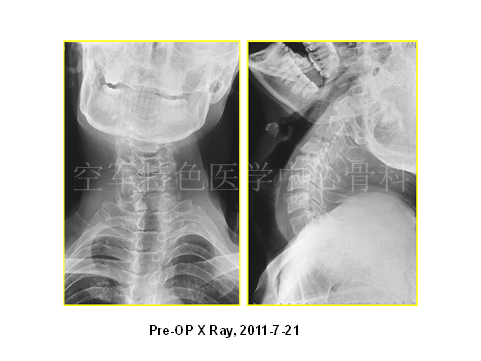

患者影像学资料如下:

介绍患者疾病情况后,陈宇飞医师邀请大家对进一步诊疗进行讨论:(1)患者目前的主要诊断是什么,颈椎间盘突出症?颈椎管狭窄症?脑瘫后遗症?脊髓亚急性联合变性?(2)治疗方案如何选择,是保守治疗,还是手术治疗,手术方案是什么?

最终陈医生采取的治疗方案与各位专家不谋而合,患者最终行颈后路C3-6椎管扩大成型术,术后患者自觉症状明显减轻,JOA评分:12分。术后3年随访,患者步态稳健,无明显不适。

随访影像学如下: